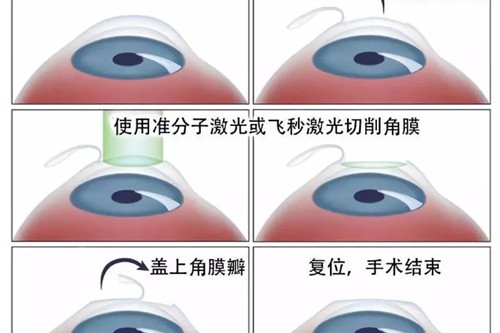

视网膜脱落的治疗方法有多种。对于尚未发生脱离的视网膜裂孔,可采用激光治疗,利用激光封闭裂孔,防止视网膜脱落。传统的巩膜环扎术和巩膜外加压术,适用于单纯的早期视网膜脱离。

而对于病情复杂的视网膜脱落,如伴有玻璃体混浊、牵拉等情况,玻璃体切割视网膜复位联合手术是常用的治疗方式。

这种手术对技术要求高,需要特殊的设备及术后护理。此外,渗出性视网膜脱离主要以治疗原发病为主。